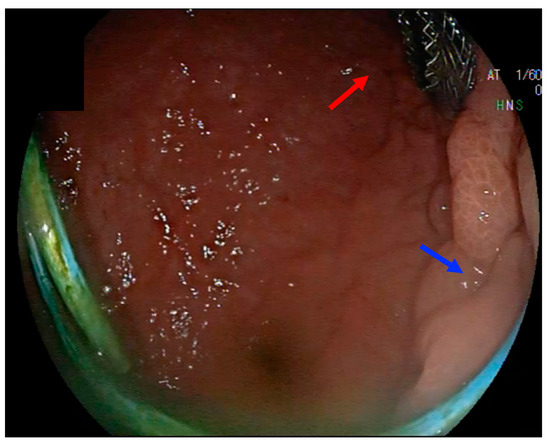

10. Direct Endoscopic Necrosectomy